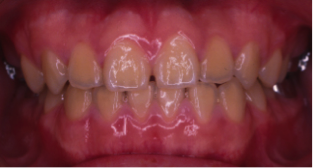

過蓋咬合(かがいこうごう)※ 非抜歯

20歳/女性

悩み:噛み合わせが深い

下の前歯が上の歯茎に食い込んでいる状態

治療期間:約2年

治療前

治療後

深い噛み合せを改善する治療が必要になりました。

先に深い噛み合せを上げないと矯正装置がつかないので、噛み合せの深さを改善する治療から行なう矯正治療となりました。